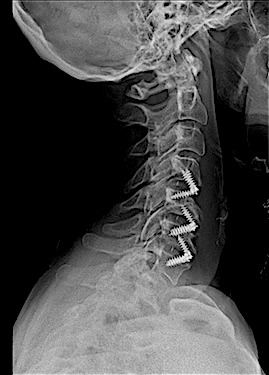

En mi opinión, las cajas intersomáticas atornilladas (CISA) son la mejor opción para corregir la cifosis cervical anterior, especialmente en patología multinivel. Además, a diferencia de «Cage Stand Alone» o caja cervical + placa; la lordosis conseguida se mantiene mejor en el tiempo.

En la técnica quirúrgica es clave asegurar una descompresión adecuada y respetar al máximo la anatomía de los platillos cervicales lo que, en algunos casos de espondilosis avanzada, es laborioso.

Aquí presento dos ejemplos.